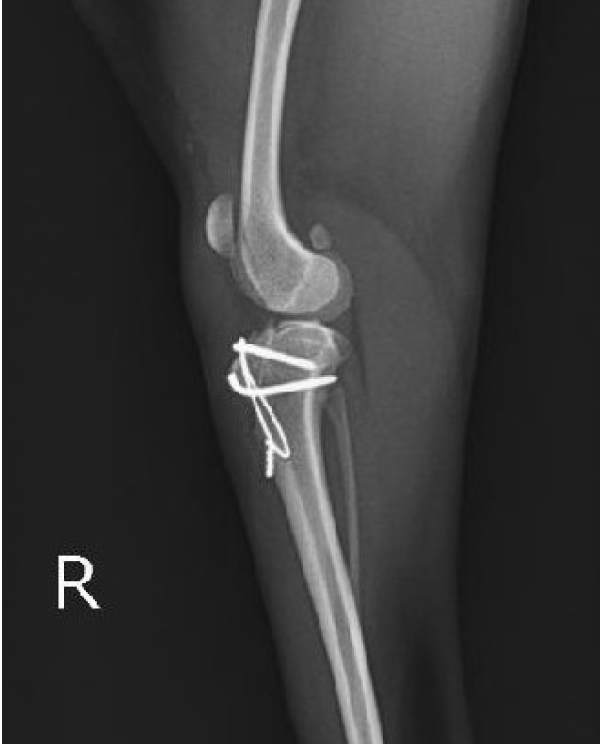

膝蓋骨は膝のお皿、パテラなどともよばれる膝の骨で、足の骨(大腿骨)の溝を上下に動くことで足は屈伸することができます。この膝蓋骨が溝から外れてしまう状態を膝蓋骨脱臼といい、外れ方により内方脱臼、外方脱臼と分類されます。小型犬の成長期での発症が多いですが全犬種で見られます。症状は、無症状、軽度の跛行、顕著な痛み、重度では脚の変形など様々です。靱帯損傷の合併症を起こすと急性の症状悪化が起こります。

治療は外科(複数の手術方法を組み合わせる方法)や内科療法など程度によって様々です。